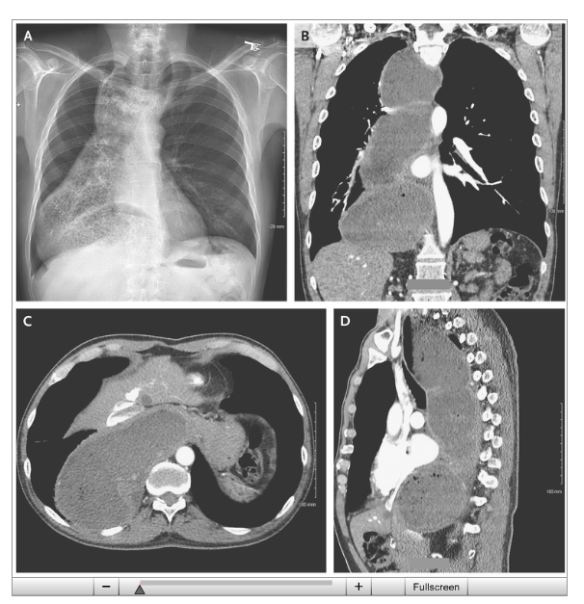

Achalasia with Megaesophagus

From NEJM twitter feed: Achalasia with Megaesophagus (in a 63 yo)